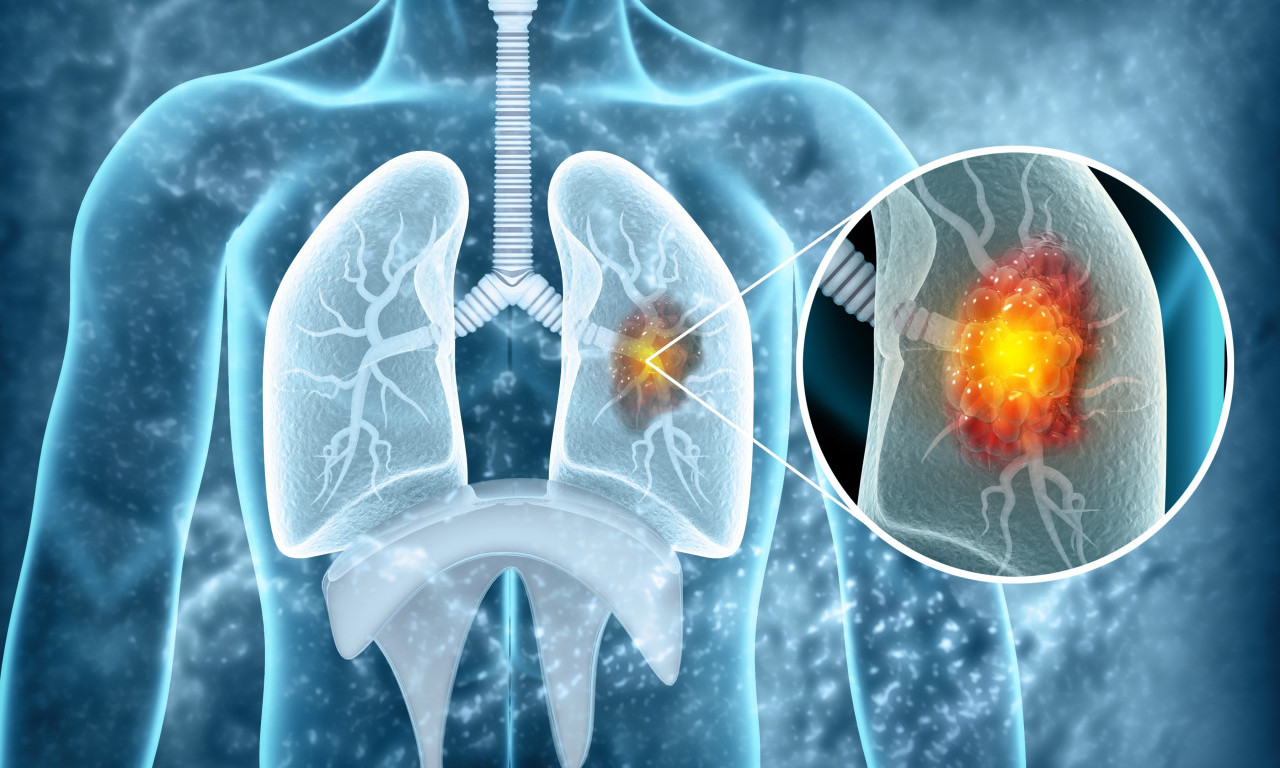

VEŠTAČKA INTELIGENCIJA OTKRIVA RAK PLUĆA MESEC DANA UNAPRED! Potrebno je uraditi osnovne medicinske analize

Da li je NOVI LEK rešenje globalnog problema? Lekari objavili da najefikasnije zaustavlja RAK PLUĆA

Rak pluća je vodeći uzrok smrti od raka u svetu, a godišnje ima 1,8 miliona smrtnih slučajeva od kancera pluća

ALARMANTNI PODACI U SRBIJI! Od RAKA PLUĆA oboli 7.000 SRBA godišnje, što nas stavlja na drugo mesto u Evropi

CRNA STATISTIKA: 70% obolelih RAK PLUĆA otkrije tek kad su ŠANSE ZA IZLEČENJE MINIMALNE, ovo je NAJVEĆI PROBLEM

Doktor je objasnio koje metode lečenja postoje u Srbiji i na koji način se određuje da li će pacijent biti podvrgnut inovativnom lečenju